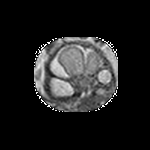

Exp. 3: Adult thorax data: To show the versatility of our approach we also apply it to adult thorax scans. For this experiment no organ specific training is performed but the whole volume is used. We evaluate reconstruction performance similar to Exp. 1 and Ti^^subscript𝑇𝑖\hat{T_{i}} prediction performance when ΩΩ\Omega is projected on an external plane, comparable to X-Ray examination using C-Arms. The latter provides insights about our method’s performance when applied to interventional settings in contrast to motion compensation problems. 60 healthy adult thorax scans were randomly selected, 51 scans used for ΩtrainsubscriptΩ𝑡𝑟𝑎𝑖𝑛\Omega_{train} and nine scans used for ΩvalidationsubscriptΩ𝑣𝑎𝑙𝑖𝑑𝑎𝑡𝑖𝑜𝑛\Omega_{validation}. Each scan is intensity normalised and resampled in a volume of 200×200×200200200200200\times 200\times 200 with spacing 1mm×1mm×1mm1𝑚𝑚1𝑚𝑚1𝑚𝑚1mm\times 1mm\times 1mm. Using the Fibonacci sampling method, 25 sampling plane of size 200×200200200200\times 200, evenly spaced between -50 and +50, were rotated over 500 normals. Training took approximately 20 hours for 60 epochs. Fig. 4c shows an example reconstruction result gaining 28dB PSNR with additional SVR. Ti^^subscript𝑇𝑖\hat{T_{i}} prediction takes approx. 20 ms/slice for this data.

Figure 4: (a): Comparison of a single slice from raw low-dose thorax CT data; (b): reconstruction based on SVRNet Ti^^subscript𝑇𝑖\hat{T_{i}} regression; (c): SVR initialized with SVRNet transformations after four iterations of SVR; (d): PSNR of (b) and (c) compared to (a). (e): shows a projection of an unseen pathological test CT volume as DRR and (e) shows a DRR at the location predicted by our method when presented with the image data in (e).

We use Siddon-Jacobs ray tracing [15] to generate Digitally Reconstructed Radiographs (DRRs) from the above described data. For training, we equally sample DRRs on equidistant half-spheres around 51 CT volumes at distances of 80cm, 60cm, and 40cm, between 90superscript90-90^{\circ} and 90superscript9090^{\circ} around all three co-ordinate axes. For validation, we generate 1000 DRRs with random rotation parameters within the bounds of the training data at 60cm distance from the volumetric iso-centre. We trained on healthy volunteer data and tested on nine healthy and ten randomly selected pathological volumes (eight lung cancer and two spinal pathologies). Our approach is able to predict DRR transformations relative to the trained reference co-ordinate system with an average translation error of 106mm and 5.6superscript5.65.6^{\circ} plane rotation for healthy patients, and 130mm and 7.0superscript7.07.0^{\circ} average error for pathological patients. An example is shown in Fig. 4e,f. Note that these values are good enough to robustly initialize intensity-based registration refinement. SVRNet prediction can be improved by generating a denser training data set, in particular, in more equidistant half-spheres.